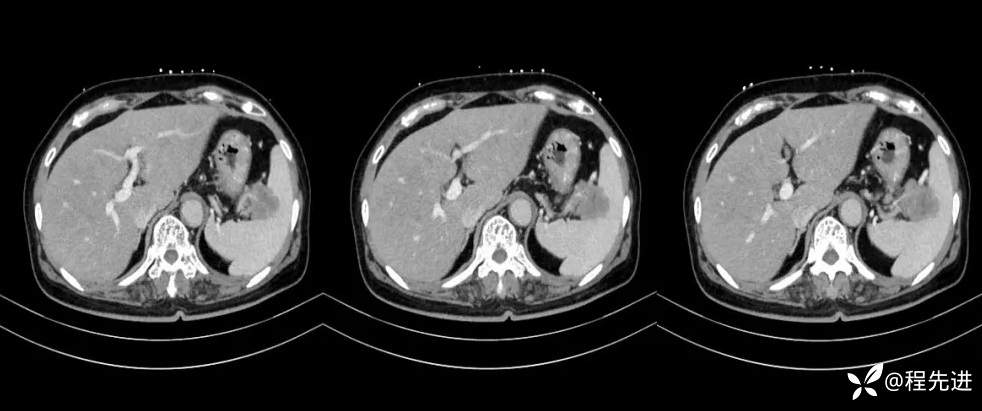

【现病史及既往史】:体检发现胰尾部肿块4年,当时手术病理提示异常增生性病变,现发现右侧顶部包块,逐渐增大,无明显感觉不适

影像检查: